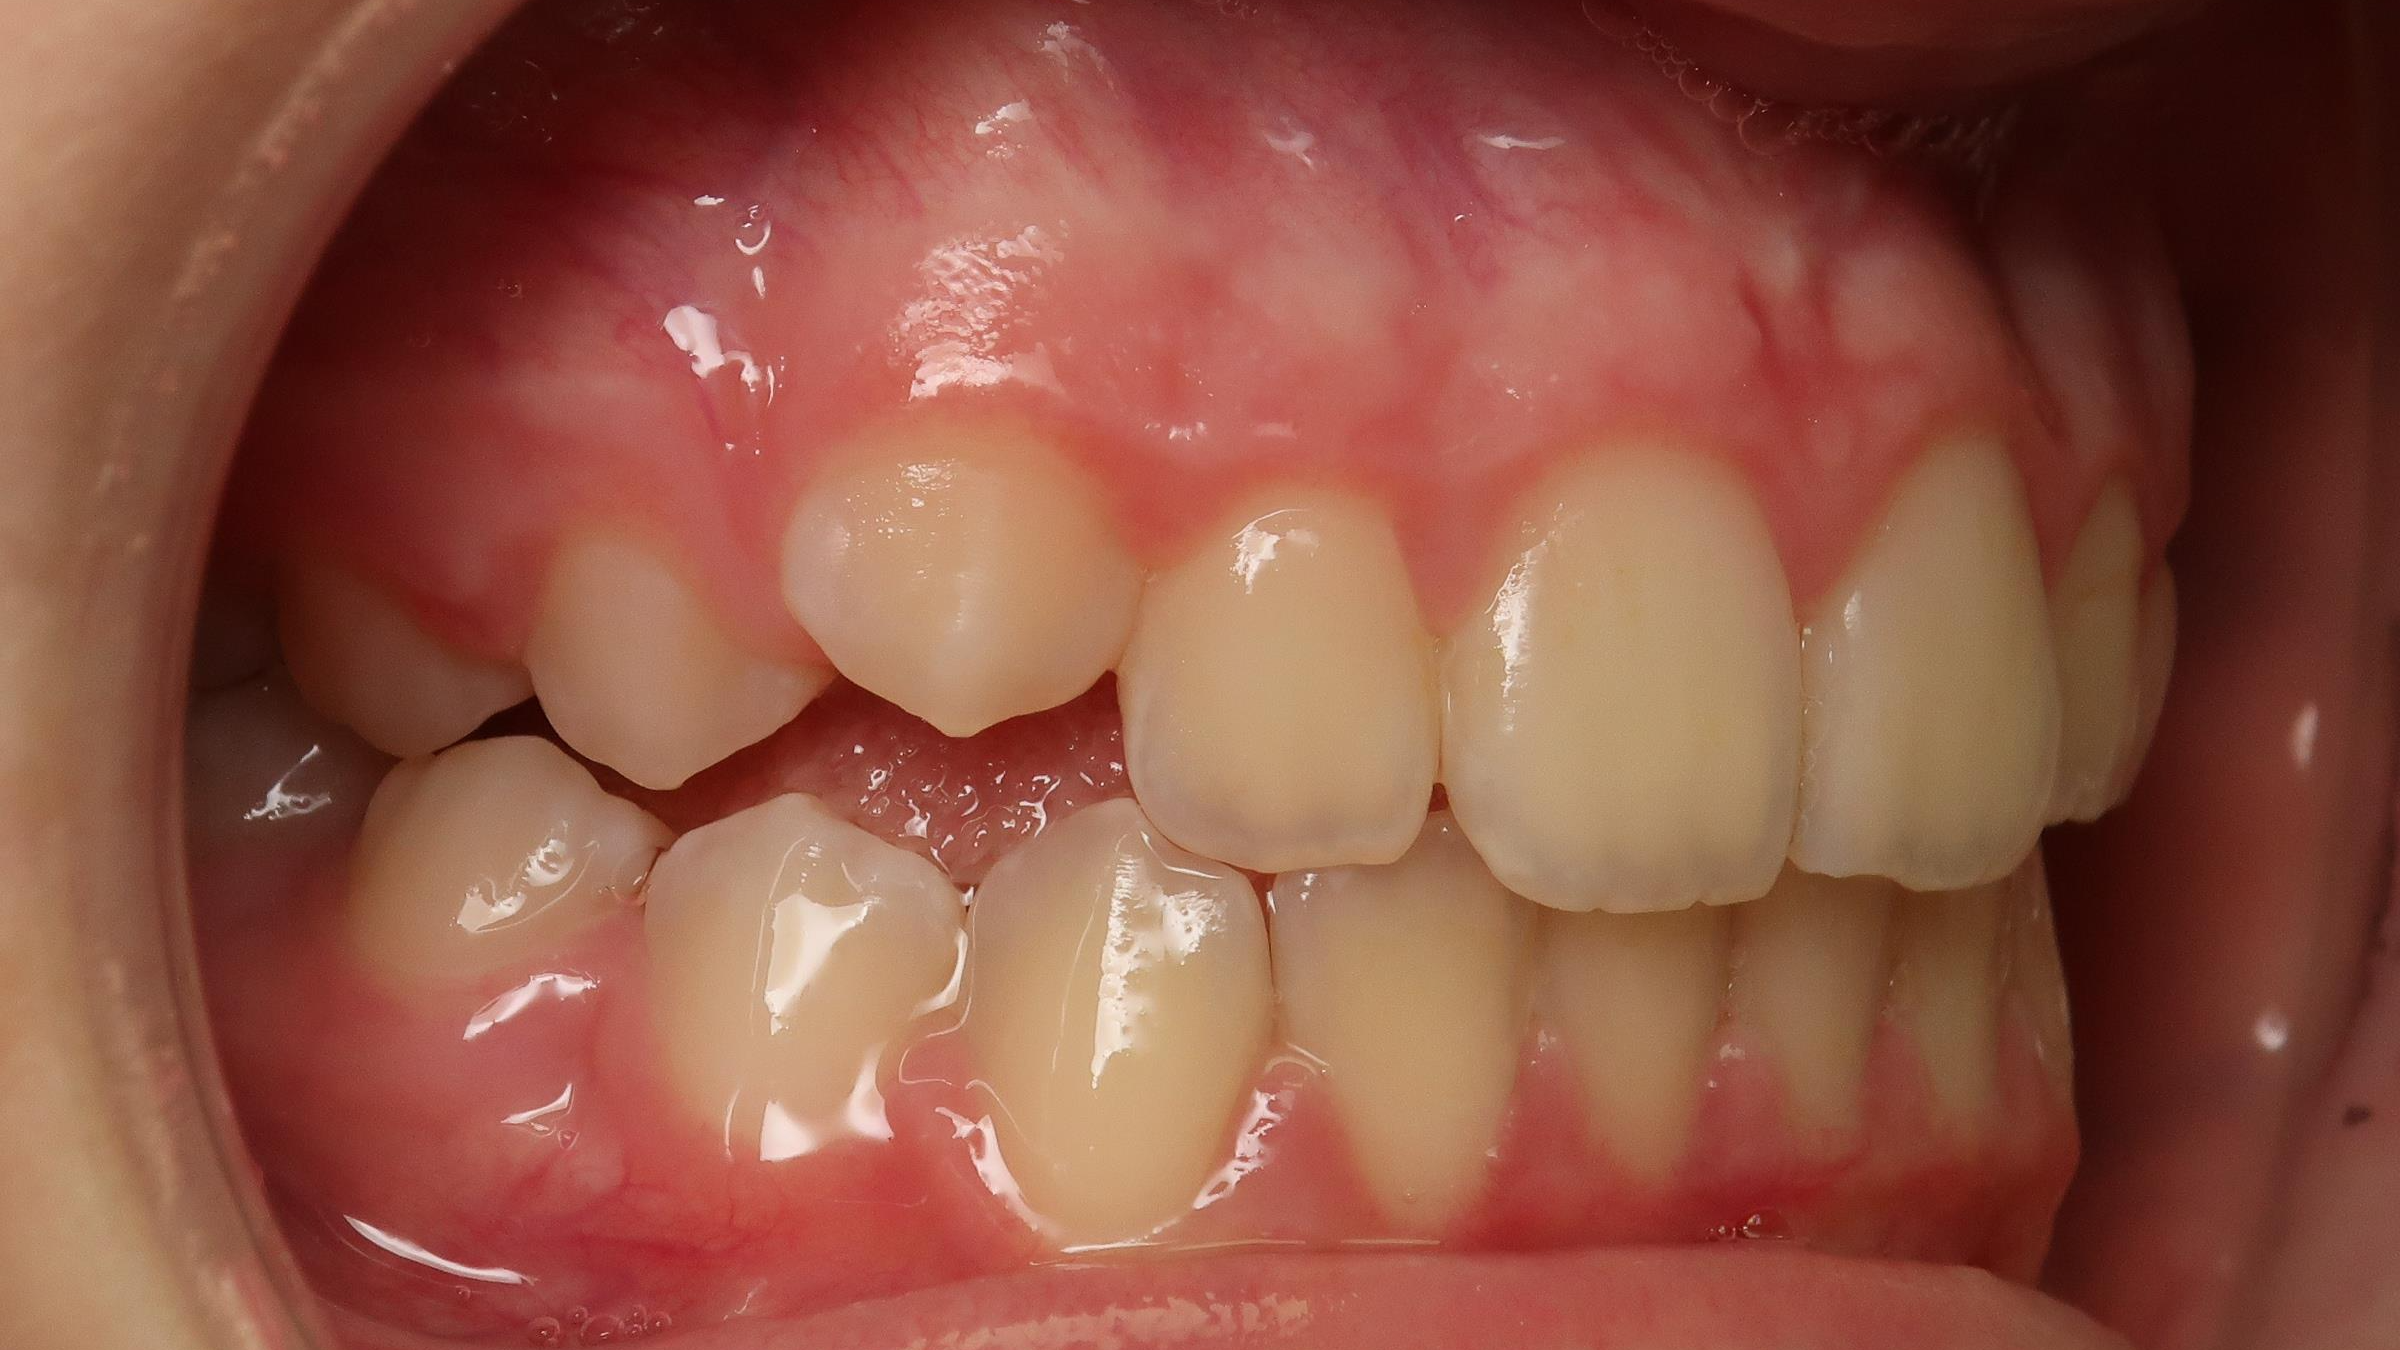

sectionnel multibagues pendant 8 mois

bilan de début et en cours de traitement